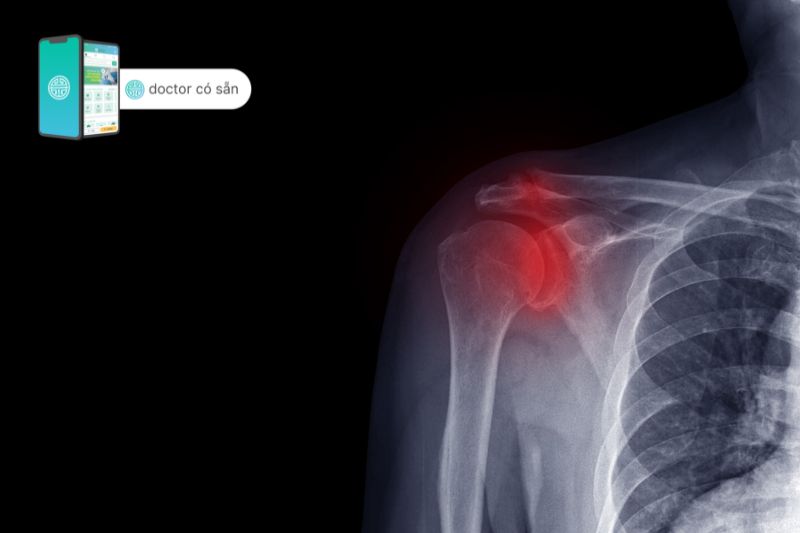

- Nếu bác sĩ nghi ngờ bạn bị thoái hóa khớp vai, họ thường sẽ yêu cầu chụp X-quang vai để tìm dấu hiệu hao mòn trên khớp.

- Xem xét các nghiên cứu hình ảnh khác, chẳng hạn như MRI hoặc CT, thường sẽ cho thấy không gian khớp hẹp hoặc sự hình thành các vùng xương phụ được gọi là gai xương do xương cọ xát với nhau.